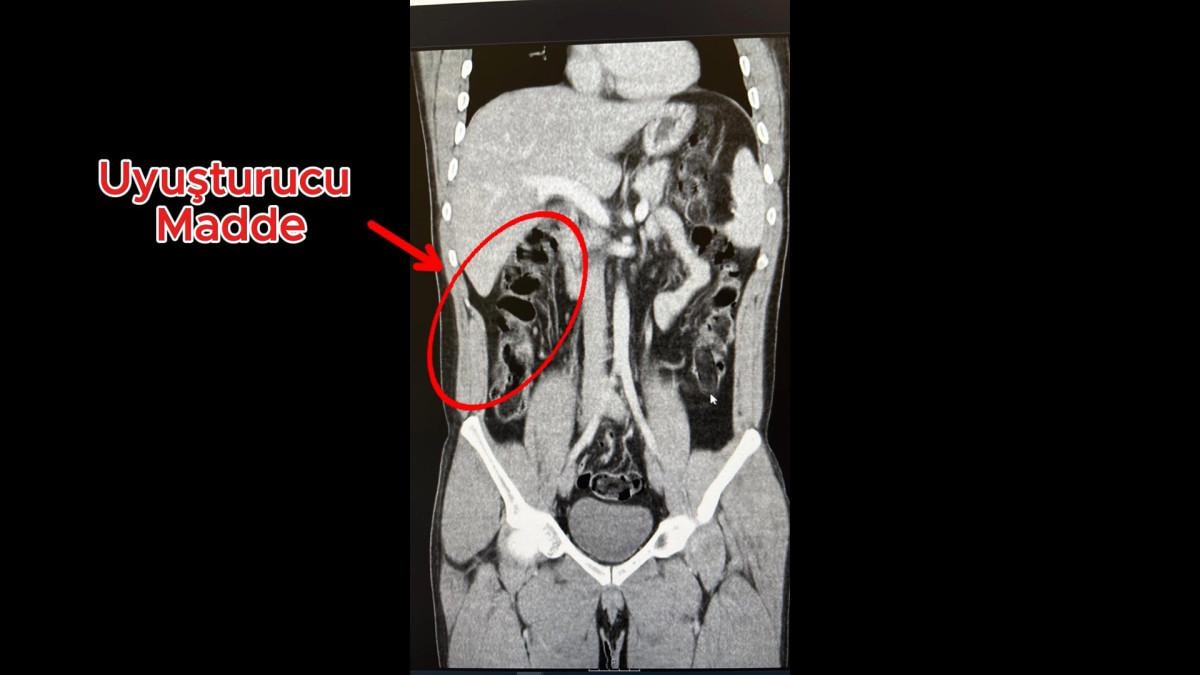

Hastanedeki iç beden muayenesinde, 2 şüphelinin, toplam 278 gram 35 kapsül halinde eroini yuttuğu saptandı.

Şüphelilerin havalimanındaki görüntüleri, muayene edilme anları ve yuttukları kapsüllerin yer aldığı film sonuçları, kameralara yansıdı.